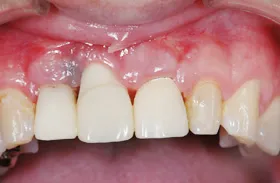

むし歯による前歯欠損の為来院されたケース

■治療前

■歯の根の引き上げ

■治療後

治療のポイント

歯の根の位置を引き上げ、抜歯。その日にインプラント治療へ。

自然の歯と変わらない審美性を取り戻し、非常に満足されています。

| 主訴 | 上顎の真ん中の歯が折れた |

| 治療方法 | 歯の根を引き上げることにより、増骨するので、その後1本のインプラントを埋入し治療した |

| 治療期間 | 約1年 |

| 通院回数等 | 10回 |

| 費用 | 550,000円(税込) |

| リスク・副作用 | 外科治療なしで増骨させた為、治療期間が長くなった |